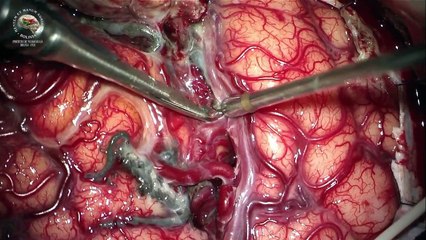

NEUROCIRUGÍA VASCULAR – CIRUGÍA DE BASE DE CRÁNEO

CIRUGÍA DE COLUMNA VERTEBRAL